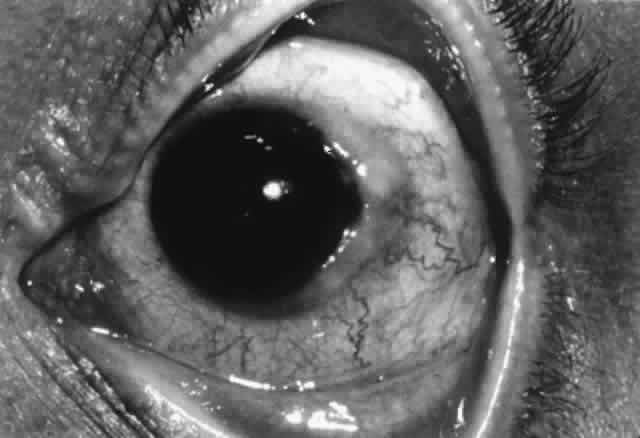

Although epithelial rejections and subepithelial infiltrates do not cause significant graft damage by themselves, they signal that endothelial graft rejection may follow and should be treated with topical corticosteroids.

Topical corticosteroids are the first line of treatment for endothelial rejection. Typically, prednisolone acetate 1% is given every hour while awake, and dexamethasone ointment is used at bedtime. More severe rejection episodes may be supplemented with subconjunctival dexamethasone, oral prednisone, or pulse IV methylprednisolone.129,139,169 Oral or topical cyclosporine can be used to prevent graft rejection in high-risk cases.170,171 Cyclosporine will undoubtedly offer a therapeutic option for corneal graft rejection as well. Cytotoxic agents are used infrequently.

It is often impossible to differentiate graft edema caused by nonimmunologic endothelial loss from that caused by graft rejection. Thus, if there is any doubt, any graft edema should be treated as possible rejection with topical corticosteroids.